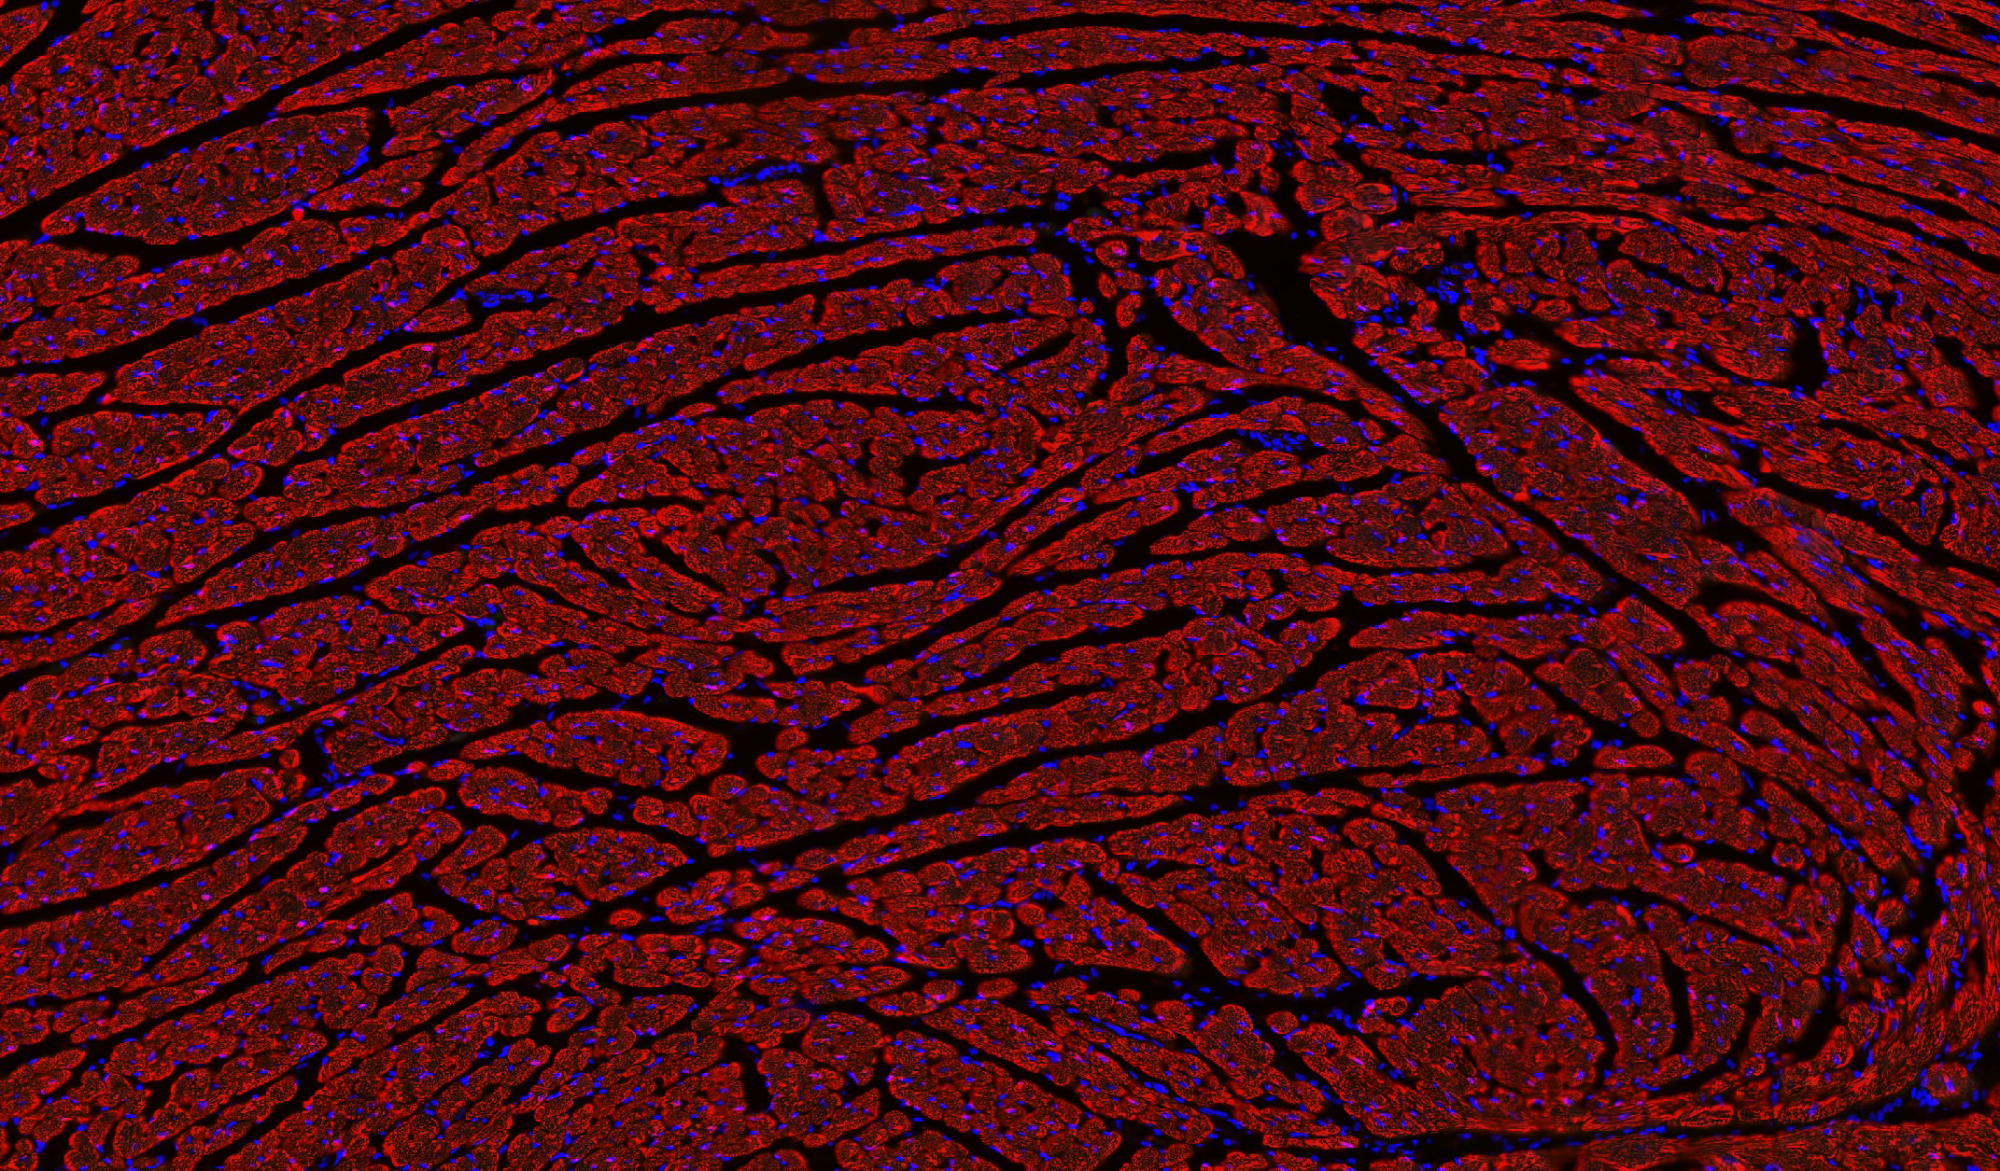

病理平臺(tái)可承接:石蠟切片,切片掃描,熒光掃描,HE染色,各種特殊染色,如:Masson、油紅O、PAS、番紅O、ALP、TRAP、甲苯胺藍(lán)以及免疫組化/熒光、原位雜交等,3D HISTECH滿足對(duì)結(jié)果高質(zhì)量,高標(biāo)準(zhǔn),周期快的實(shí)驗(yàn)外包需求,并提供染色培訓(xùn)服務(wù),分線上視頻,線下實(shí)操帶教兩種培訓(xùn)方案。